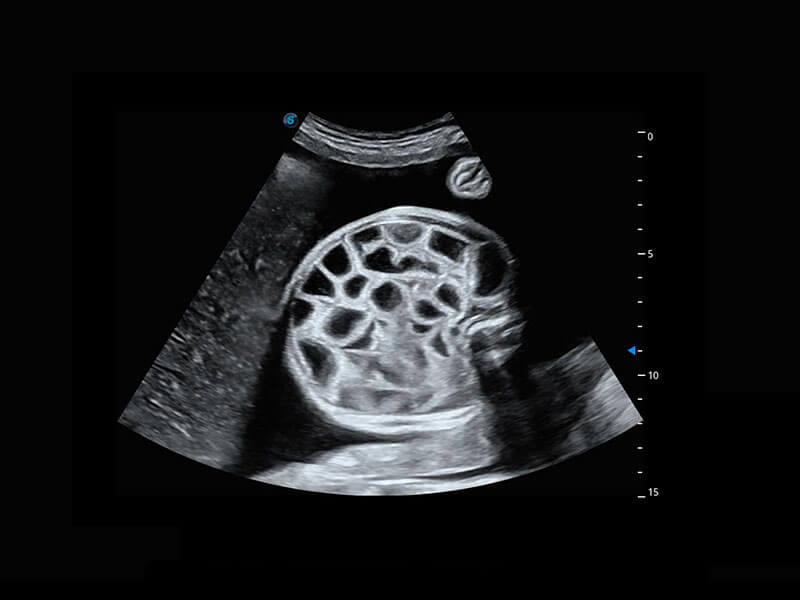

高分辨率容积成像-早孕胎儿

P60在胎儿早孕期超声筛查中为您带来优异的图像质量。

P60提供简单易学易用的高端诊断工具,为您中晚孕筛查提供快速清晰的解剖信息。